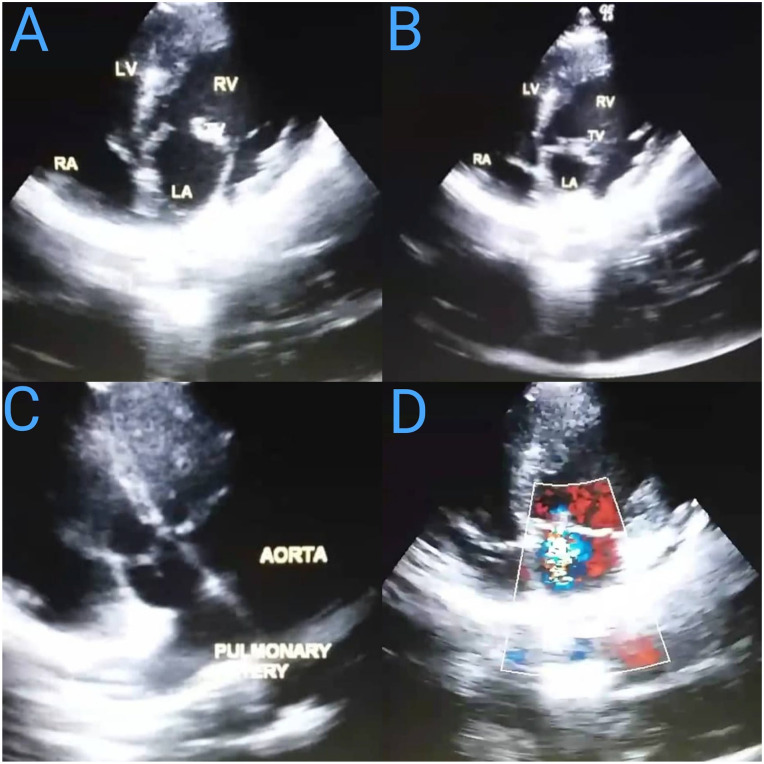

Congenitally corrected transposition of the great arteries (ccTGA) is a complex cardiac abnormality that represents less than 1% of all congenital heart defects. It is characterized by a unique pathophysiology involving both atrioventricular and ventriculoarterial discordance and may occur with or without cardiac abnormalities such as ventricular septal defects, pulmonary stenosis, or tricuspid valve anomalies. A man in his 20s presented with a 3-week history of mild dyspnea during strenuous activities. The patient was diagnosed with isolated ccTGA based on electrocardiogram and echocardiogram findings. However, as a long-term complication of ccTGA, the patient exhibited mild tricuspid regurgitation, mild mitral regurgitation, and right ventricular hypertrophy. The dyspnea was explained by the failing systemic right ventricle. Despite his cardiac anomaly, the patient leads a normal lifestyle, with ongoing monitoring to ensure optimal management of his condition. ccTGA is even rarer in the absence of additional cardiac abnormalities, and its diagnosis could be delayed due to being asymptomatic. Patients must avoid risk factors and that could potentially aggravate their condition. Regular surveillance is imperative for the early detection of potential complications.